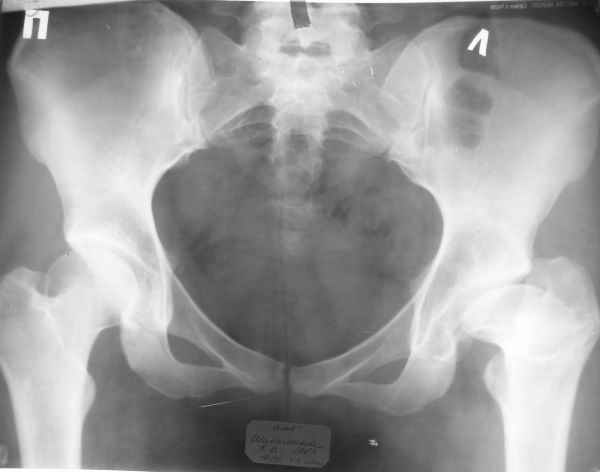

Пациентка 23 лет, доставлена в клинику с Диагнозом: Закрытый сегментарный оскольчатый перелом левой бедренной кости в верхней и средней трети. Травма в результате ДТП 10.03.2006г. Из анамнеза у пациентки диспластический левосторонний коксартроз, S-образный сколиоз 2ст. В 1999г в Кургане выполнялась остеотомия бедра в нижней трети и коррекция укорочения конечности на 3 см (рентгенограммы бедра и таза до травмы в приложении). До получения травмы пациентка ходила без боли с полной нагрузкой на левую ногу. Учитывая дисплазию левого ТБС, пациентке, вероятно, предстоит операция тотального эндопротезирования лев ТБС, что требует анатомичного восстановления проксимальногоотдела бедра. Рассматриваются следующие вариант остеосинтеза:1) Экстракортикальный остеосинтез проксимального и дистального перелома пластиной с угловой стабильностью типа LISS( г Рыбинск); 2) Ретроградный интрамедуллярный блокированный остеосинтез дистального перелома и накостный синтез проксимального пластиной с угловойстабильностью; 3) Остеосинтез бедра в аппарате внешней фиксации с фиксацией таза и возможной открытой адаптацией фрагментов. Хотелось бы узнать Ваше мнение. С уважением Украинский Евгений, г.Краснодар, ККБ N1, ТОО N3.

Не во всех случаях, особенно у молодых!, при дисплазии ТБС требуется эндопротезирование. По представленным снимкам четко видны хорошо сохраненный тазобедренный сустав и тем более больная до травмы не имела симптомов диспластического сустава. В будущем при появлении симптомов, можно попытаться сделать реконструктивную работу по сохранению сустава: ПАО с удлинением шейки (аналогичные случаи были

Учитывая, что в проксимальная часть бедра в скором будущем будет нуждаться в больших оперативных вмешательствах, я бы старался сохранить проксимальное кровообращение бедра и поэтому считаю антеградное штифтование неприемлемым методом для данного случая.

Я бы персонально для фиксации выбрал бы короткий DHS или Blade Plate и ретроградное штифтование (регенерат после удлинения!, трудности с просверливанием), вторым вариантом оставил бы пластину с угловой стабильностью (Polyax, Synthes и т.д) с перкутанным методом внедрения, репозиция отломков по усмотрению автора: на ортопедическом столе, на бедренном дистракторе или дистракторе из двух колец от аппарата Илизарова. Главное, обратить внимание на ротацию конечности во время